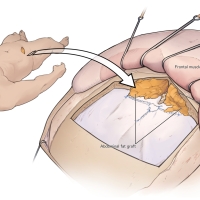

術後イラストシリーズ